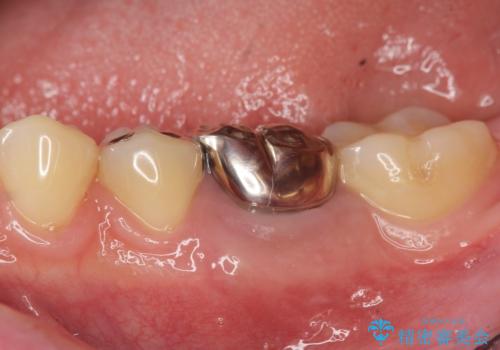

![[ 2次カリエス ]クラウンのグラつき クラウン下の虫歯再発の症例 治療前](https://seimitsushinbi.jp/wp/wp-content/uploads/2022/06/4ae3379503827b239da023fb595493f5-500x350.jpg?v=1655105440)